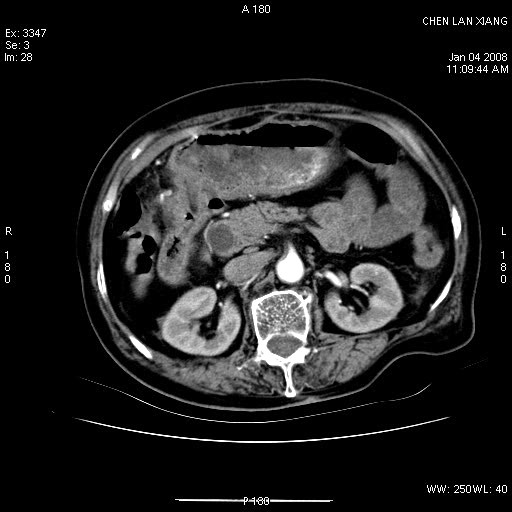

女,76岁,腹痛3-4天,b超示:肝内实性肿物,胆囊强回声,胆总管扩张.

考虑:1、胆总管下端结石伴梗阻性肝内外胆管扩张(肝左叶外侧段肝内胆管多发结石、胆管炎);

2、肿囊癌累及肝,不除外 黄色肉芽肿性胆囊炎。

1 胆总管末端结石伴肝内胆管结石,肝内外胆管扩张。2 胆囊扩大,胆囊壁不规则增厚,内见软组织密度影。考虑:慢性胆囊炎,不除外胆囊癌!

胆囊内结增强影,肝内胆管、胆总管扩张明显。肝内胆管、胆总管下段多发结石,胆囊癌,建议mrcp检查

ct所见:1、 肝内胆管结石,肝内外胆管扩张。低位胆道梗阻,胆总管下端结石;2 胆囊扩大,胆囊壁不规则增厚

考虑:胆总管下端结石并肝内外胆管扩张,肝内胆管结石;